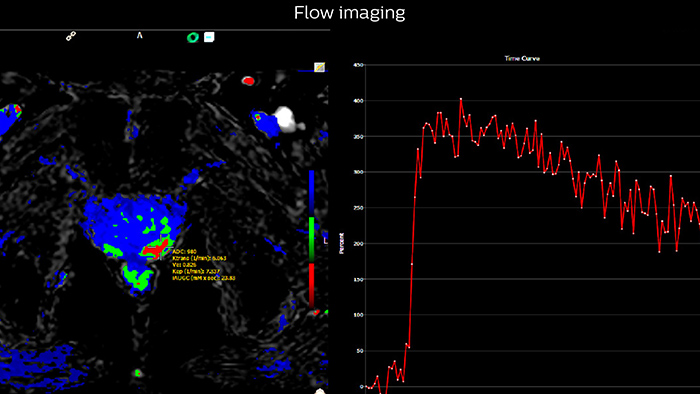

“The third characteristic we look at, flow, is somewhat less specific but may be quite important in deciding whether a lesion is significant or insignificant. Prostate neoplasms often have a hypervascular tumor flow pattern, meaning that there is rapid inflow of blood into the lesion and then rapid outflow due to a disrupted capillary bed. This can be graphed on multi-parametric images, allowing us to define regions of interest and look at the actual flow within these regions.”

Multiparametric MRI of a classic peripheral zone lesion Dr. Steiner describes this case: “For lesions in the peripheral zone of the prostate, the DWI (diffusion weighted imaging) and ADC map are most helpful for diagnosis. In this case, the DWI shows a very bright signal, which indicates diffusion restriction. The arcuate area with significant signal drop out (arrow) on the ADC map is recognized as highly suspect for tumor. On the axial T2-weighted image the capsule contour looks a little irregular (arrow), which we interpret as capsular disruption, and I usually give a measurement: this lesion shows larger than 1.5 cm capsular disruption. I don’t see any signs of lymphadenopathy, but interpret this lesion as PI-RADS 5. The hypervascular flow pattern in the bottom images adds to the diagnostic confidence.”